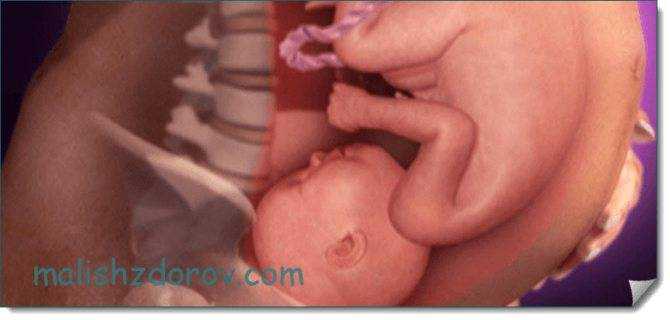

С каждым днем размеры плода увеличиваются, из-за чего места в животике становится все меньше. На этом сроке, как правило, малыши уже не переворачиваются в утробе, а их движения становятся более осознанными. В большинстве случаев ребеночек занимает головное предлежание. Иногда кроха располагается ягодицами вниз и находится в такой позиции до самых родов (тазовое предлежание).

На 29 неделе беременности на головке у малыша уже видны волосики. Сейчас они напоминают скорее пушок. Вместе с этим, пушок, который присутствовал на теле (лануго), исчезает. Уменьшается также количество защитной смазки. С каждым днем увеличивается жировая прокладка и малыш все больше становится похожим на новорожденного. Кожа приобретает светло-розовый оттенок, появляются так называемые младенческие складочки и милая припухлость на щечках.

Внешне, ребенок на 29 неделе беременности выглядит почти так же, как после рождения. Пушок на его коже начинает исчезать, а количество первородной смазки уменьшается к моменту родов. Доля подкожного жира на этой неделе ничтожно мала – около 4%. Однако, по мере роста плода, жировая клетчатка будет активно нарастать, что способствует гладкости кожи.

Малыш в утробе матери готовится к появлению на свет. Его кровь приобретает стабильный состав, сформирован иммунитет. Костный мозг плода активно работает. И пищеварительная система малыша готова к перевариванию пищи. Уже удалились из носовых ходов пробки из слизи. Почки ребенка вырабатывают по половине литра жидкости ежедневно с выведением мочи в околоплодные воды. Дитя уже способно фокусировать взгляд и видеть свет, ощущать разные запахи. Его внешность приобретает черты младенца. Кожа постепенно расправляется, и первородная смазка тела уменьшается. Но вместе с этим нарастает подкожный жир. Половые органы до конца не сформированы, однако хорошо определяются.

На 29 неделе беременности малыш выглядит уже почти как новорожденный. Набирать вес и готовить к самостоятельной большой работе легкие — вот основная задача ребенка на последние недели беременности. У малыша на этом сроке уже сформированы зрение, слух, вкус и обоняние, он может различать свет и тьму, но полностью сфокусировать зрение ему еще пока не удается. Умение это в полной мере покорится малышу к моменту появления на свет.

Сейчас плод уже может чувствовать и вкус и запах околоплодных вод; различать свет и звуки; он полностью чувствует настроение и общее состояние матери; может сфокусировать свой взгляд на чем-то одном. Внешне малыш уже начинает походить на новорожденного кроху: его кожный покров светлеет и выравнивается, лануго постепенно начинает сходить, а количество смазки минимизируется. Подкожного жира становится больше и чем ближе к дате родов, тем больше милых складочек образуется на теле ребеночка.